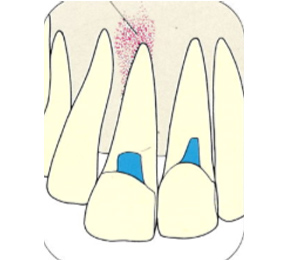

こちらのレントゲン写真を見てください。どちらかの歯医者さんで神経を取っています。根管に入れる薬は白く映ります。赤矢印部分です。一番右側が模式図ですが、青い部分が薬、根っこの先の赤点が化膿している部分です。

薬がほとんど入っていないのがわかります。黄矢印部分です。青矢印まで薬が入らないといけないのですが、全く入っていません。その結果、根っこの先が黒くなっています。膿が貯まって化膿すると黒く写ってくるのです。

別な歯科医院で治してもらいました。薬が根の先まで入っているのがわかります(黄矢印)。 根尖の黒い影が消失しています(赤矢印)。骨が再生すると白く写るようになります。

ガッタパーチャポイントは、理想的には歯根(シコン)の先ピッタリが良いと言われています。

しかし先ほど説明したように根管(コンカン)の形態は非常に複雑怪奇です。なので一概にピッタリが良いと限らないケースもあります。

ここでは一応、根尖(コンセン)付近が良いということにしておきましょう。

上の図にあるように神経の管に入れる薬が根尖(コンセン)まで入っていなかったり、途中までしか入っていなかったり、薬がスカスカだったりするとその空間にばい菌が繁殖して感染を起こします。

そうすると神経を取ったはずなのに、その後歯ぐきが腫れて痛くなるのです。

この根っこの病気を根尖性歯周炎というのです。そしてこの根尖性歯周炎を治すことを感染根管治療と言います。

大事な話なのでもう一度説明します。

①の写真はどちらかの歯医者さんで神経を取ってもらったレントゲン写真です。根っこの中に薬が全く入っていません。

②の模式図で青く描かれている部分が薬です。

根の先を見ると小豆ぐらいの大きさの黒い影が見えます。根の中でばい菌が繫殖し感染を起こすとこのような黒い影ができます。黒い影の部分は膿(ウミ)が貯まっています。こうなると腫れて痛みが出てくるのです。

③、④の写真はそれを治した後のレントゲン写真とその模式図です。白く映っている薬が根の先まできちんと入っているのが確認できます。そして根の先にあった黒い影が消えているのが分かります。根の先の炎症が治って、骨が再生すると白く映るのです。

実はこのケース、歯医者さんの神経を取る治療でこのような根っこの病気になってしまったのです。そこでこの患者さんは神経を取った歯医者さんではなく、別の歯医者さんに受診して、根っこの治療をして治したのです。